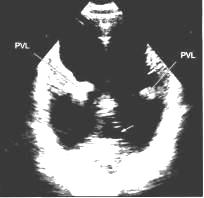

Эхокадіографія (УЗД) - сьогодні

найважливіший і інформативний метод дослідження, який дозволяє поставити точний

діагноз. Завдяки УЗД вперше в історії з'явилася пряма можливість побачити серце

дитини до пологів, а сучасні методи дозволяють діагностувати вроджену ваду

серця при вагітності усього в кілька тижнів. Насамперед помітні вади, при яких

будова серця різко порушена, тобто дуже важкі й складні для виправлення надалі.

Г,й)

У народженої дитини УЗД дозволяє

визначити наявність або відсутність структурних змін. Крім того, дає можливість

визначити тиск у порожнинах серця, різницю тиску між камерами, установити

величину й напрямок скидання крові, якщо він є, товщину стінок передсердь і

шлуночків. Й)

УЗД дає можливість спостерігати за

перебігом вади серця в динаміці - тобто бачити, що відбувається із серцем , як

воно реагує, у якому напрямку йдуть зміни - до поліпшення або, навпаки, до

погіршення. Іншими словами, воно може дати сигнал - чи треба активно

втручатися, щоб допомогти, і коли, щоб не було занадто пізно. І, якщо

врахувати, що метод цей - неінвазивний, абсолютно безпечний і може бути

повторений неодноразово й безболісно - то зрозуміло, що він став основою

сьогоднішньої діагностики. А, є,й)